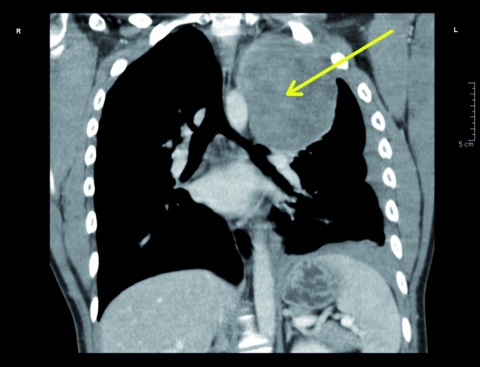

In der Nacht stellte sich ein 25-jähriger Mann in der zentralen interdisziplinären Notaufnahme des Bundeswehrkrankenhauses (BwKrhs) Ulm vor. Er war aus einer nahegelegenen Klinik aufgrund von atemabhängigen linkseitigen Thoraxschmerzen mit unklarem röntgenologischen Befund zugewiesen worden. Bei der Anamnese berichtete der Patient, dass er wenige Stunden vor der ersten Arztvorstellung beim Sport einen plötzlichen linksseitigen thorakalen Schmerz verspürt habe. Dieser sei persistent, atemabhängig und wurde von ihm mit einer Intensität von 8 (numerische visuelle Analogskala von 0 – 10) beschrieben. In einer Computertomographie des Thorax (diese wurde ohne Kontrastmittel als Trauma-CT durchgeführt, da zu diesem Zeitpunkt zunächst kein Verdacht auf das Vorliegen einer Tumorerkrankung bestand) war eine hypervaskularisierte Raumforderung von 9 x 9 x 11 cm im linken Oberlappen zu sehen. Ebenso wurde bei dieser Untersuchung der dringliche Verdacht auf einen Hämatothorax geäußert. Aufgrund einer möglicherweise erforderlichen thoraxchirurgischen Intervention mit gegebenenfalls notwendiger konsekutiver intensivmedizinischer Betreuung wurde der Patient zu uns verlegt.

Die stationäre Aufnahme erfolgte aufgrund der ausgeprägten Klinik und dem Verdacht auf das Vorliegen eines Hämatothorax. Hinzukam die thorakale Raumforderung mit unklarer Genese, deren Ätiologie abzuklären war. Zunächst ging man hierbei von einer eingebluteten Zyste aus; des Weiteren stand eine Neoplasie mit unklarer Differenzierung im Raum. Zur Histologiebestimmung wurden einige Methoden diskutiert, wobei sich eine Thorakoskopie als am besten geeignet ergab. Diese war im weiteren Verlauf geplant.